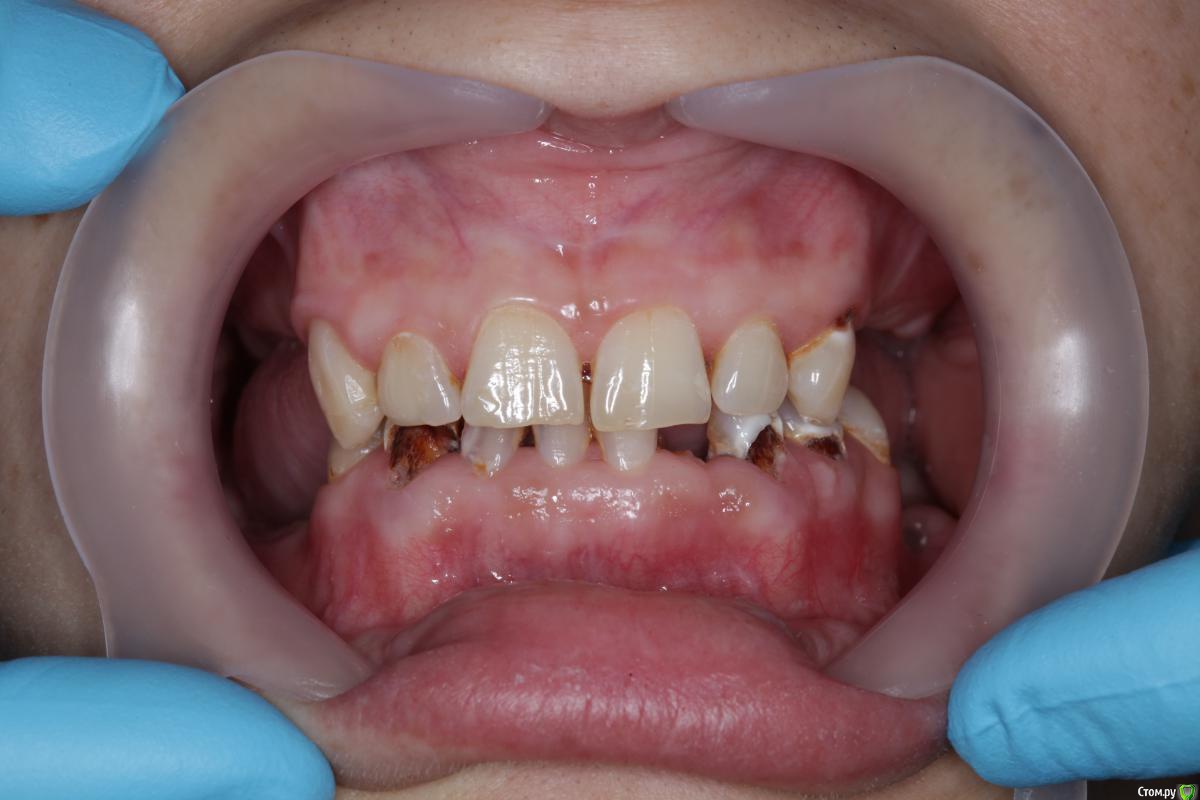

faity Опубликовано 27 июля, 2015 Поделиться Опубликовано 27 июля, 2015 (изменено) 1.8, 1.7, 2.8, 3.8, 3.6, 4.8 под снос, имплантация и тоталтотал можно оверлеем без девитализации ЕМах на все зубы, кроме 3.1, 4.1, 4.2, на них виниры Изменено 27 июля, 2015 пользователем faity 1 Ссылка на комментарий

DmitrySH Опубликовано 29 июля, 2015 Поделиться Опубликовано 29 июля, 2015 1.8, 1.7, 2.8, 3.8, 3.6, 4.8 под снос, имплантация и тоталтотал можно оверлеем без девитализации ЕМах на все зубы, кроме 3.1, 4.1, 4.2, на них виниры Ну как сейчас можно планировать ортопедию, оверлеи или нет.???Сперва тут удаления и тотальная терапия, убрать все рыхлое, по показаниям где-то эндо. Где-то витальными оставлять, но без фанатизма. 1 Ссылка на комментарий

Bratok Опубликовано 29 июля, 2015 Поделиться Опубликовано 29 июля, 2015 Поднимать прикус планируете и как если да ? Ссылка на комментарий

gum Опубликовано 30 июля, 2015 Поделиться Опубликовано 30 июля, 2015 Так в итоге какой прогноз, кто таких протезировал. У меня сейчас девушка с такой картиной, у эндокринолога лечится. С ее слов. Жду заключения врача. Так у нее дентин весь мягкий эмаль крошится. Кроме как все удалять есть еще варианты? Так как коронки потом падать начнут. Ссылка на комментарий